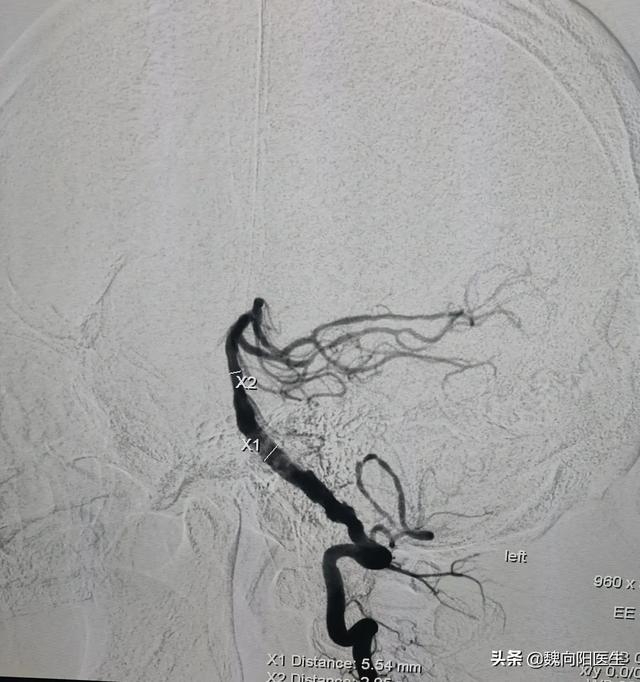

Les vertiges causés uniquement par un apport sanguin insuffisant au cerveau sont généralement considérés comme une ischémie de la circulation postérieure. C'est généralement un rétrécissement ou une occlusion de l'artère vertébrobasilaire qui entraîne une ischémie cérébelleuse. Dans les cas graves, cela peut conduire à un infarctus de la circulation postérieure.

Dans ce cas, la plupart d'entre eux doivent être réveillés pour une dilatation/stentation par ballonnet de l'artère vertébrobasilaire afin d'améliorer la sténose ou l'occlusion des artères circulatoires postérieures et d'améliorer la perfusion des cellules cérébrales.

Il est également nécessaire de contrôler les maladies sous-jacentes telles que l'hypertension, le diabète sucré, l'hyperlipidémie, l'hyperhomocystéinémie, etc. pour prévenir l'athérosclérose des artères vertébrales basilaires.